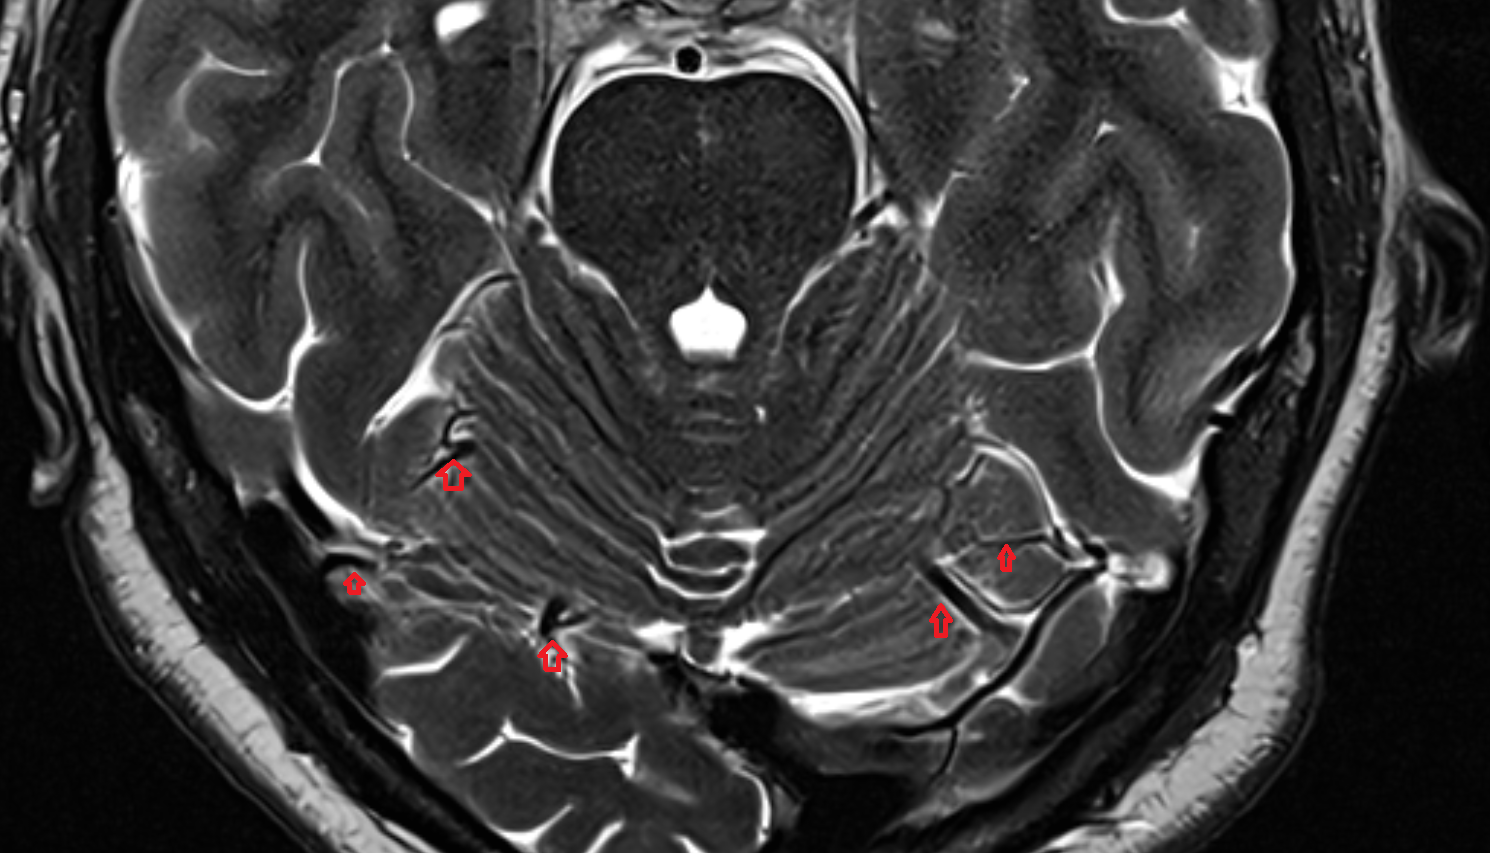

- Cerebellum